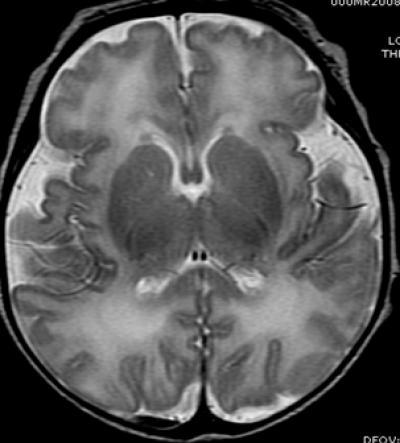

This image shows anatomy (MRI) -- 15 weeks premature.

(Photo Credit: Radiological Society of North America)